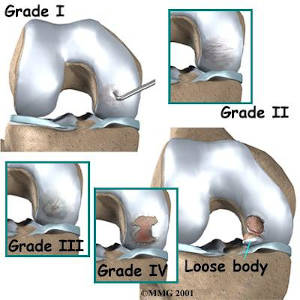

Οι επαναλαμβανόμενοι μικροτραυματισμοί των πλέον βεβαρημένων αρθρώσεων και κυρίως του γόνατος και η διαταραχή αιμάτωσης που αυτή προκαλεί μπορεί να οδηγήσει σε διαχωριστική οστεοχονδρίτιδα (osteochondritis dissecans).

Εκτός της υπερκαταπόνησης προδιαθεσικοί παράγοντες για την εμφάνισή της είναι η έλλειψη vitD, και γενετικοί εμβιομηχανικοί παράγοντες, χωρίς όμως να υπάρχει σαφής αιτιολογία. Η γρήγορη διάγνωση σε πρώιμα στάδια, η απομόνωση εκλυτικών παραγόντων η αποφόρτιση και κινησιοθεραπευτικό πρόγραμμα ελαττώνουν σημαντικά το χρόνο αποχής από την άθληση. Σε προχωρημένα στάδια απαιτείται χειρουργική αποκατάσταση.